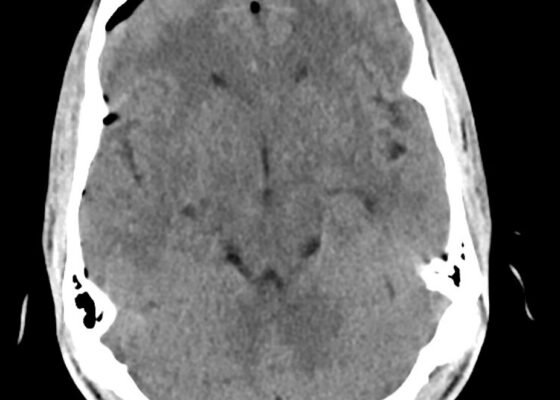

A Different Type of Tension Headache: A Case Report of Traumatic Tension Pneumocephalus

DOI: https://doi.org/10.21980/J8DH0GCT head without contrast demonstrated a minimally displaced fracture of the frontal sinuses at the midline underlying his known laceration that involved the anterior and posterior tables of the calvarium. This is seen on the sagittal view and indicated by the blue arrow. There was a small volume of underlying subarachnoid hemorrhage along the falx. There was also extensive pneumocephalus most pronounced along the bilateral anterior frontal convexity associated with the frontal sinus fracture, seen on the axial image and indicated by the red arrow. This pattern of air is commonly referred to as the “Mount Fuji” sign.6 Other intracranial air can also be seen on the sagittal image and is indicated by the white arrow.